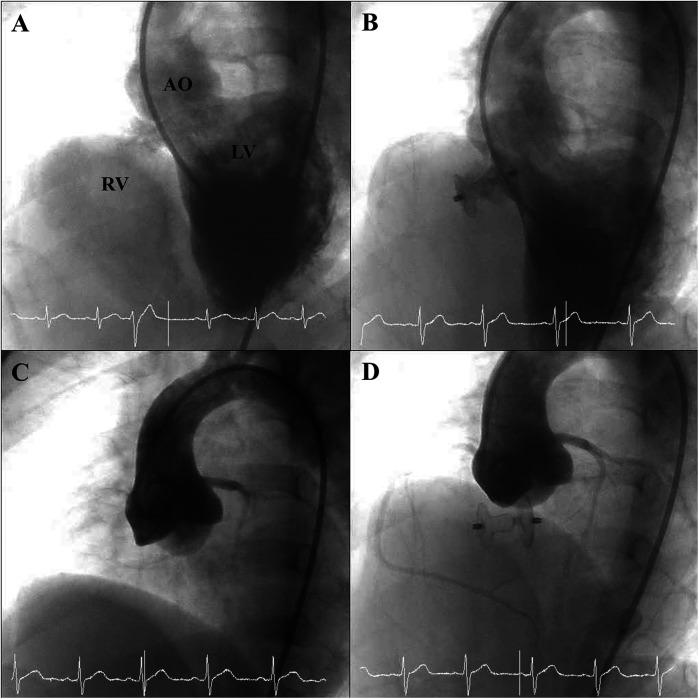

A total of 115 patients (52.2% male) underwent transcatheter PmVSD closure. The median age was 7.6 years [interquartile range (IQR), 4.0-27.2] and weight 25.6 kg (IQR, 14.2-62.6). Median defect size by angiography was 5.7 mm (IQR, 3.8-8.3) on the left ventricle side and 3.3 mm (IQR, 2.3-4.4) on the right ventricle side. Aortic valve prolapse (AVP) was noted in 114 patients (99.1%), with pre-procedural aortic regurgitation (AR) in 36 (31.3%). Median pulmonary artery pressure was 17 mmHg (IQR, 14-20); 48 (41.7%) had Qp/Qs >1.5. All procedures were successful; 33 (28.7%) used a retrograde approach. Median fluoroscopy time was 22 min (IQR, 15-33). Complete closure was achieved in 51.3% at 1 day, 62.6% at 1 month, 69.6% at 3 months, and 83.5% at 6 months. Transient conduction disturbances ( = 4), hypotension ( = 1), and femoral hematoma ( = 1) were observed. No cases of endocarditis, valve injury, or complete atrioventricular block occurred.

Transcatheter closure of PmVSD with the MFO demonstrated safety and efficacy during the 6-month follow-up period. Notably, the majority of defects in this cohort were small in size.